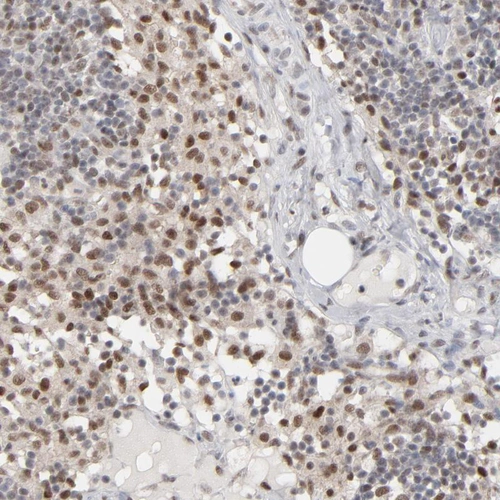

Immunohistochemical staining of human lymph node shows moderate nuclear positivity in non-germinal center cells.